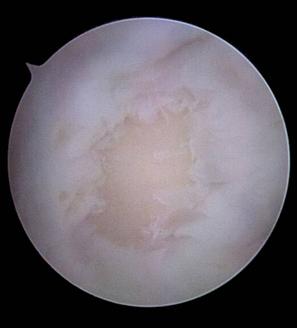

1.3. Diagnosticul Artroscopic al leziunilor cartilajului articular

Examinarea artroscopica a genunchiului ramine standardul de aur in diagnosticarea si evaluarea leziunilor cartilajului articular. Examenul artroscopic permite evaluarea suprafetei cartilajului, a rezistentei la presiune, dar mai ales a marimii si profunzimii zonei leziunii condrale. Numeroase sisteme de clasificare a leziunilor cartilajului articular au la baza examinarea artroscopica directa a acestuia (vezi capitolul 2).

Examinarea artroscopica a cartilajului permite evaluarea mai multor caracteristici ale acestuia. Rezistenta cartilajului la presiune se efectueaza cu ajutorul exploratorului (probe), si se refera la forta cu care acesta este impins inapoi dupa ce presiune a incetat. Persistenta unei depresiuni condrale este semn de "inmuiere" a cartilajului. Artroscopic se evalueaza si culoarea cartilajului care normal este alba, lucioasa, cu usoara tenta galbuie. Cartilajul artrozic are o culoare galbuie marcata, este mat.

La examinarea artroscopica suprafata cartilajului este neteda, lucioasa, o fara discontinuitati. Pierderea luciului, prezenta unor depresiuni, fisuri, fibrilatii, delaminari sint semne de leziune. De asemenea, o zona de ingrosare a cartilajului, depresibila la examinarea cu exploratorul, este semnul unei leziuni profunde: "blister".

Fig. 1.15 Imagini artroscopice - osteocondrita disecanta: in stinga fragment condral partial detasat , in dreapta patul osos ramas dupa indepartarea fragmentului osteocondral detasat, se observa ca leziunea condrala este mai extinsa decit cea osoasa |